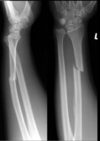

Fratura de Bennett

Fratura da base do primeiro metacarpo;

Intra-articular;

Dois fragmentos.